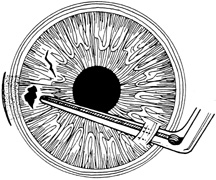

Tissue adhesive should be applied to a dry, deepithelialized bed. A capillary microapplicator or fine-gauge disposable needle is used to apply a very thin film of adhesive over the site (Fig. 3). Alternatively, adhesive may be applied using a sterile 2- to 4-mm polyethylene or silicone disc affixed to the end of an applicator stick with sterile ophthalmic ointment. The disc may be left in place or removed with care. Three to five minutes are required for polymerization of the adhesive. A bandage soft contact lens is applied for comfort and to prevent the glue from dislodging. While the contact lens is in place, a prophylactic antibiotic drop is administered. Over time, the tissue adhesive dislodges spontaneously as the wound surface reepithelializes. Alternatively, it may be gently removed with forceps after adequate stromal healing has occurred.